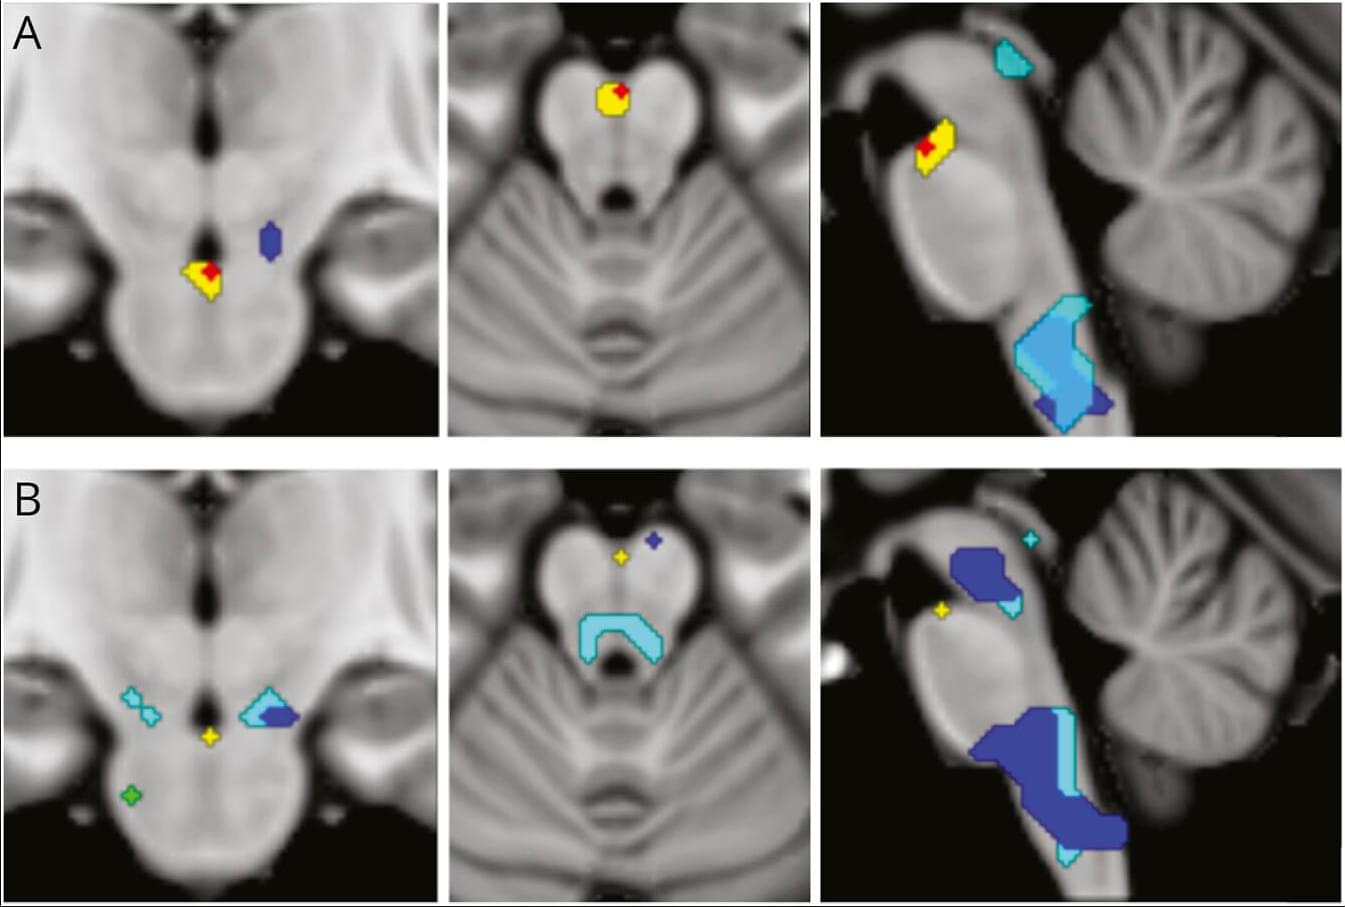

BACKGROUND: Lmods (leiomodins) are critical for the assembly and maintenance of thin filaments in striated muscles by allowing thin filament elongation at the pointed ends. Lmod2’s elongation function has been linked to both actin-binding sites (ABSs) 2 and 3, while the existence and function of an N-terminal ABS1 has been debated. METHODS: To elucidate the little-known role of Lmod2’s ABS1, we created a mutant (F64D/L69D/W72D/W73D: Lmod2-quadruple mutant) predicted to decrease the binding of ABS1 to actin. We analyzed the effect of the mutations using several in vitro, cellular, and in vivo assays. RESULTS: By disrupting the interaction of Lmod2 ABS1 with actin in isolated cardiomyocytes and in mice, we engineered a super Lmod2 that results in remarkably longer thin filaments.